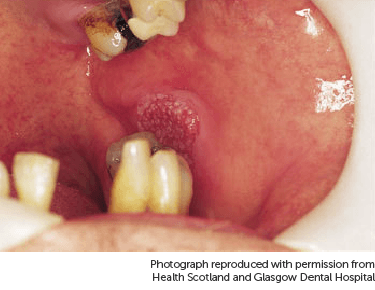

Below is a picture of a shallow ulcer on the lower lip.